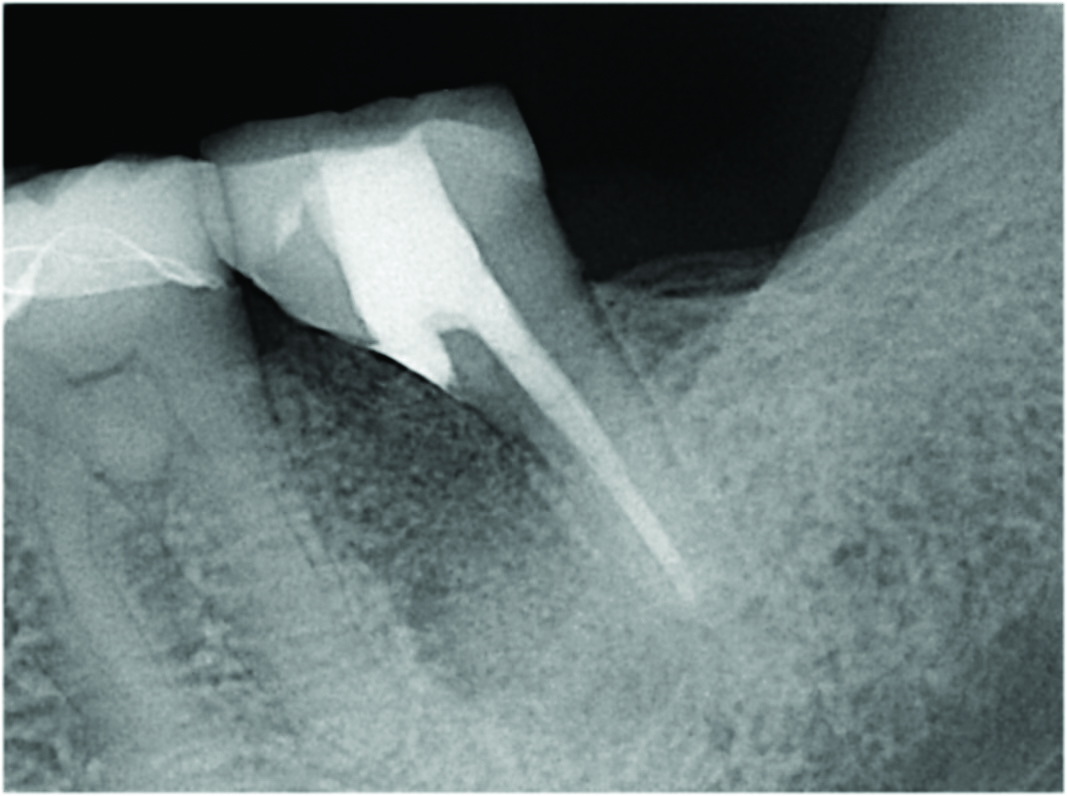

While grafting can be placed into a socket such that the level of the graft is in contact with the cantilevered portion of the tooth, the authors have observed that over time the crestal bone level will typically stabilize 1 mm to 3 mm below the cantilevered section (Figure 9 and Figure 10). The resultant level of the grafted crestal bone over time is dependent primarily on the patient's plaque control abilities, which are directly related to the contour achieved through the resection process, thus emphasizing the importance of proper resection and contouring during the procedure.

Fig 9. While grafting can be placed into a socket at a level that is in contact with the cantilevered portion of the tooth (Fig 9), over time the crestal bone level is expected to stabilize 1 mm to 3 mm below the cantilevered section (Fig 10).

Fig 10. While grafting can be placed into a socket at a level that is in contact with the cantilevered portion of the tooth (Fig 9), over time the crestal bone level is expected to stabilize 1 mm to 3 mm below the cantilevered section (Fig 10).